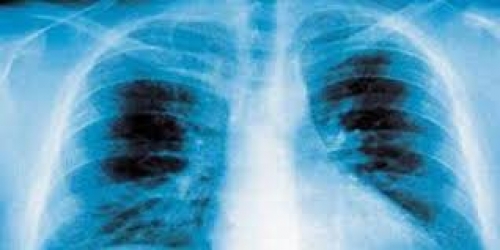

التهاب رئوى -أرشيفية

ذكر تقرير نشره الموقع الأمريكى "مايو كلينيك"، علامات وأعراض الالتهاب الرئوى فهى تختلف من خفيفة إلى شديدة اعتمادا على عوامل منها نوع الجرثومة المسببة للعدوى وعمرك والصحة العامة لجسمك، وبالنسبة للعلامات والأعراض الخفيفة للالتهاب الرئوى فهى تكون شبيهة للبرد والأنفلونزا لكنها تستمر لفترة أطول .